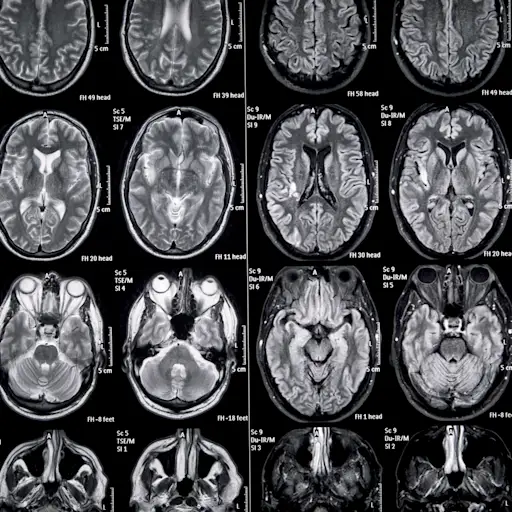

RRMS如何影响大脑?

MS导致大脑的病变,并取决于这些病变的位置,具体症状可能会有所不同。洛杉矶南加州大学的临床职业治疗助理教授Rebecca Cunningham说:“每个人都有不同的症状。“然而,最常见的认知赤字领域包括记忆,信息处理速度,关注和浓度,视觉空间能力,执行功能和口头流畅性。”您可能会很快处理信息,记住您学到的新事物,或者找到正确的词语来阐明您想说的话。